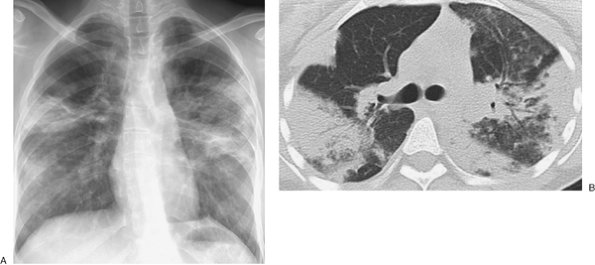

FIGURE 12-12. Cryptogenic organizing pneumonitis. A: PA chest radiograph of a 52-year-old man after bone marrow transplant for leukemia shows bilateral ill-defined parenchymal opacities. B: CT shows that the opacities are peripheral and nonsegmental. Note air bronchograms (arrows).